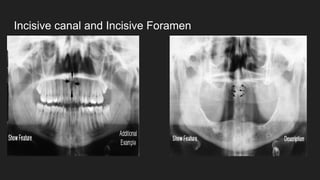

● Incisive canal

● Incisive foramen

Incisive canal and Incisive Foramen

MIDFACIAL REGION LANDMARKS Radiolucentfeatures: ● External auditory meatus ● Pterygomaxillary fissure ● Infraorbital foramen ● Orbit ● Incisive canal ● Incisive foramen ● Nasal cavity ● Maxillary sinus

Incisive canal andIncisive Foramen